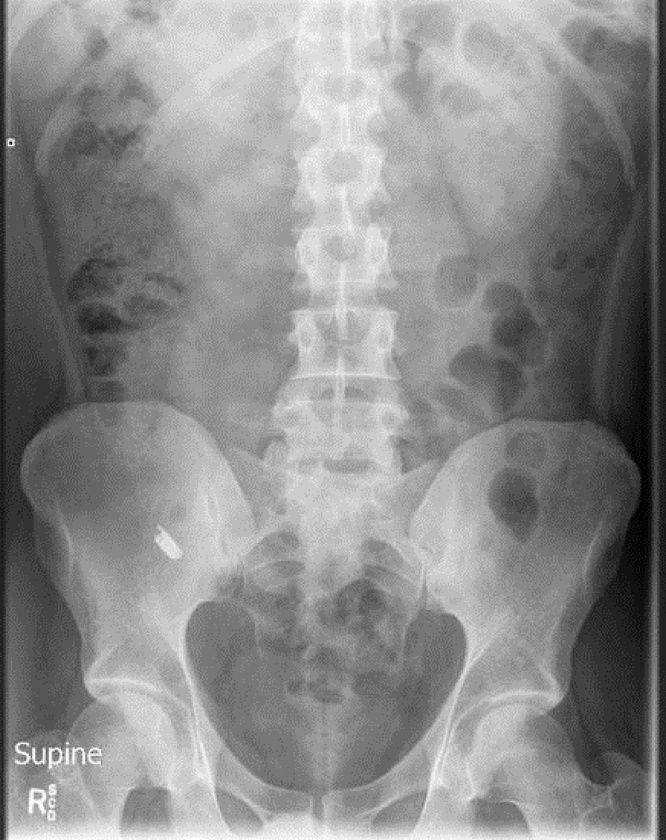

X-ray memiliki fungsi untuk memperlihatkan bagian dalam tubuh. Dengan pemeriksaan tersebut, dokter dapat mendiagnosis penyakit atau kondisi yang dialami pasien.

Namun, ada sejumlah x-ray yang merekam benda-benda tidak lazim dalam tubuh seseorang. Berikut deretan kisahnya:

1. Gelas dalam Dubur

x-ray yang menunjukkan gelas tersangkut dalam dubur. Foto: Journal of Nepal Medical Association |

Seorang pria di Kathmandu, Nepal nekat memasukkan gelas berukuran 12 cm ke dalam anus demi kepuasan pribadinya ketika mabuk. Mulanya, pria yang tak disebutkan namanya ini beralasan bahwa dia memasukkan gelas tersebut ke dalam anusnya secara tidak sengaja.

Pria tersebut akhirnya mencari bantuan setelah gagal mengeluarkan gelas tersebut dari tubuhnya secara mandiri. Kasus ini dicatat dalam Journal of Nepal Medical Association.

Dalam jurnal itu disebutkan pria ini tidak bisa buang air besar (BAB) selama dua hari. Tetapi, pria ini masih bisa buang angin.

Sementara pria tersebut dilaporkan mengalami kesakitan, perutnya tidak mengalami bengkak dan anusnya tidak mengalami cedera atau perdarahan. Hasil x-ray pria tersebut menunjukkan gelas air dalam posisi terbalik di rektum atas dan usus besar.

Tim dokter sempat mengalami kesulitan ketika ingin mengeluarkan gelas dari tubuh pria tersebut. Sebab, gelas tersebut berbahan dasar kaca dan berisiko pecah apabila ada kesalahan prosedur.

"Karena kacanya tinggi, terbalik dan terjepit rapat," ujar tim medis dikutip dari Daily Mail, Senin (27/3/2023).

Tak ada pilihan lain, dokter terpaksa memotong perut pria tersebut dan melakukan enterotomi sigmoid atau membuat sayatan di dalam usus. Cara tersebut akhirnya berhasil mengeluarkan gelas dalam perut pria tersebut.

Seminggu setelah operasi, pria tersebut diperbolehkan pulang dari rumah sakit. Janji tindak lanjut yang dilakukan dua bulan setelahnya, mengungkapkan tidak ada komplikasi.